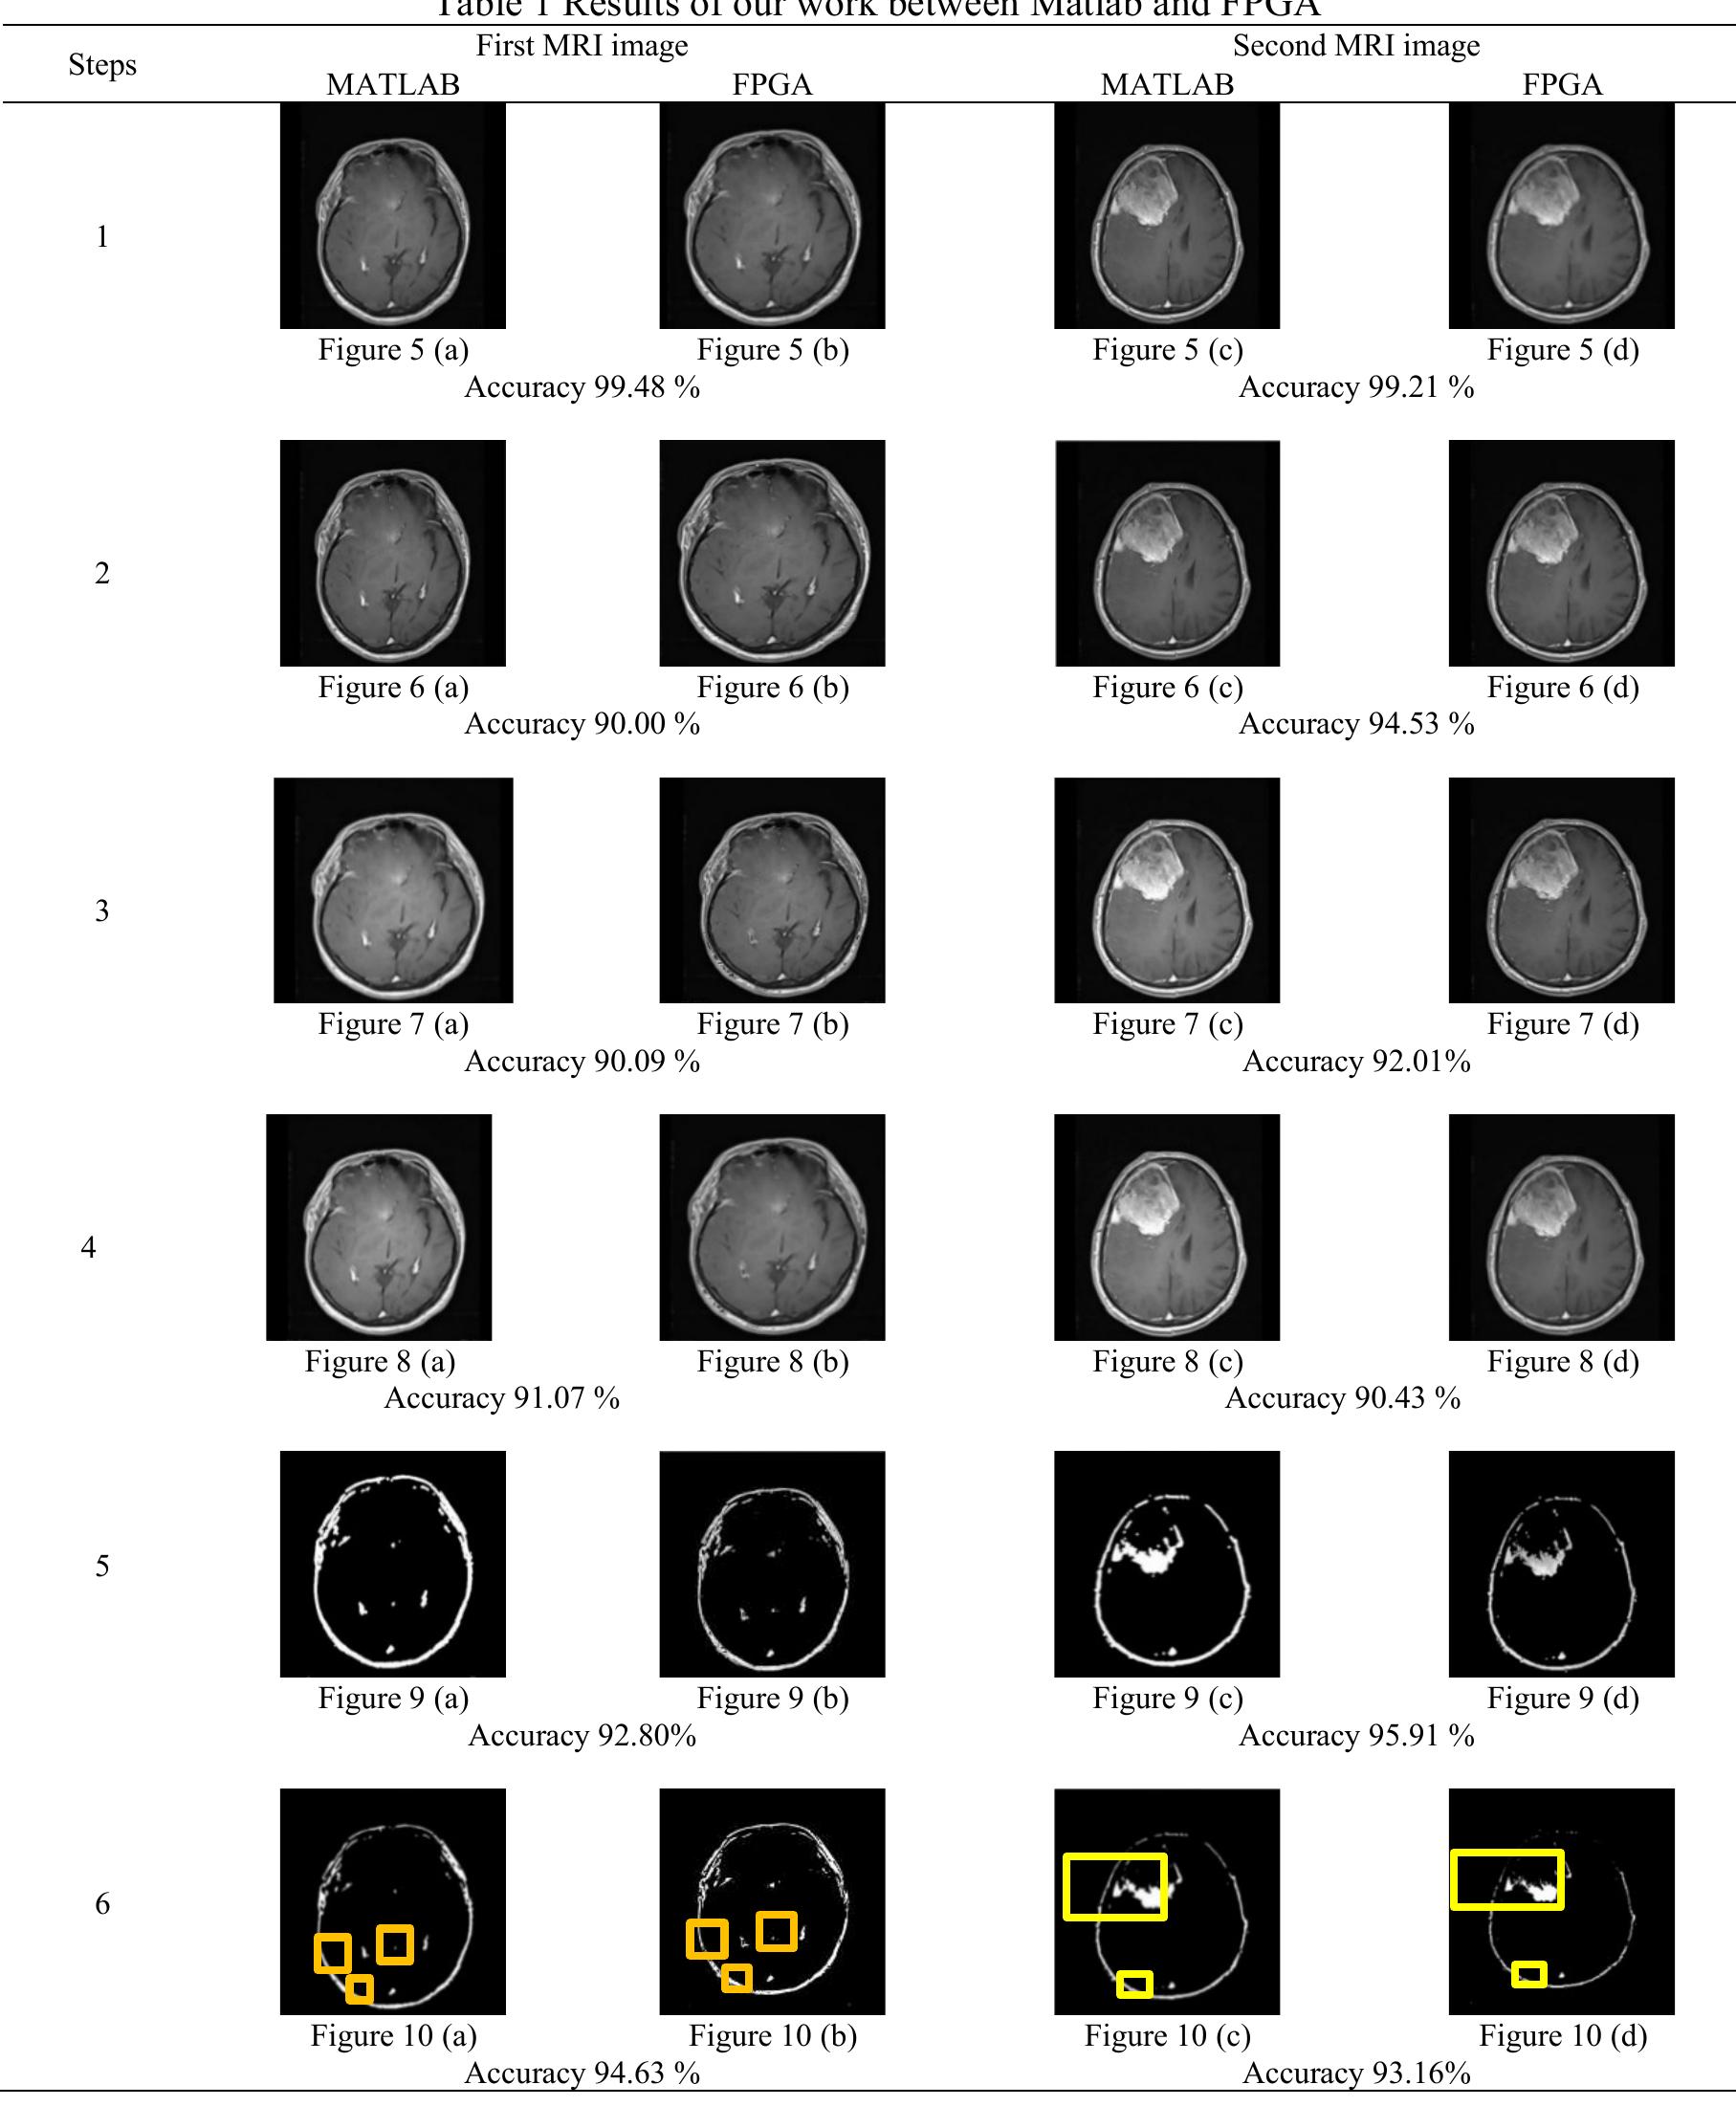

![Figure 2. Overall proposed system on zynq chip The Zynq AXI lite interface connection is used to implement the proposed system as illustrate in Figure 2. 5. RESULTS AND ANALYSIS The hardware resources for entire system are summarized in Figure 3. The Zynq xc7z020 evaluation kit comprise [30] 53200-LUT (lookup table), 106400-FF (flip-flop), 140-BRAM (block RAM), 32-BUFG, and 220-DSP (digital signal processor) block. While the implementation needs: 15% (7773) of LUT, 3% (491) of LUTRAM (RAM lookup table), 8% (8793) of FF, 6% (9) of BRAM, and 10% (23) of DSP block. In order to test the effectiveness of the proposed system, two different MRI images of brain strock are applied to our FPGA design. Then, the results are compared with Matlab program to measure the efficiency of our system as illustrated in the following flowchart: Acpocnardingo tra the Biogire 4 the flauschart inclidec the fallauzing ctenc:](https://figures.academia-assets.com/83175617/figure_002.jpg)